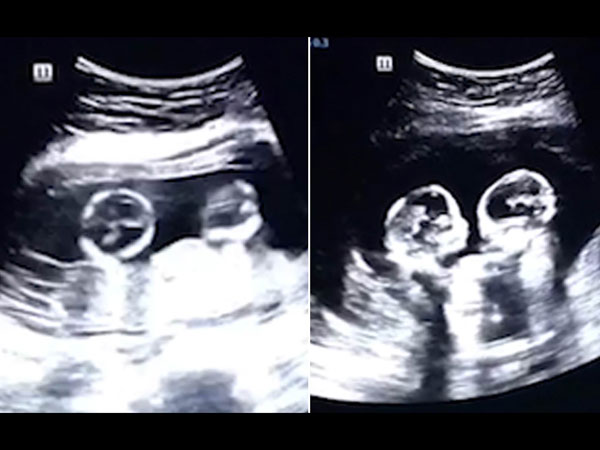

Một cặp song sinh vẫn ở trong bụng mẹ mà “chiến đấu” với nhau. Những hình ảnh này gây sốt trên cộng đồng mạng. Dù các bé chưa ra đời nhưng đã đủ "bản lĩnh" như này.

Mang thai song sinh có thể là tin tuyệt vời với nhiều người, nhưng liệu bao nhiêu người đã nhìn thấy các em bé như đang đánh nhau trong bụng mẹ. Nghe có vẻ khó tin đúng không, nhưng điều này đã xảy ra ở Trung Quốc.

Theo nguồn tin, đoạn video được lan truyền trên mạng xã hội Trung Quốc gần đây được ghi lại bởi người bố đang đưa vợ đi siêu âm. Người vợ đang mang thai 2 bé gái sinh đôi và đang ở tháng thứ 4 trong thai kỳ.

Hình ảnh siêu âm cho thấy 2 thai nhi dường như đang đá và va vào nhau liên tục. Kể từ thời điểm đăng trên Youtube, video được lan truyền rất mạnh mẽ.

Mr.Tao (28 tuổi), người bố của 2 bé gái này đã nói với trang Chinese News rằng anh cảm thấy rất thích thú với hành động của những đứa con chưa chào đời của mình. Anh còn hài hước nói rằng mình như đang xem một trận đấu quyền anh của 2 đứa con gái.

Video này ngay lập tức được chia sẻ chóng mặt trên các phương tiện truyền thông Trung Quốc. Tính tới thời điểm này video đã có hơn 2.5 triệu lượt xem và 80.000 bình luận trên mạng xã hội.